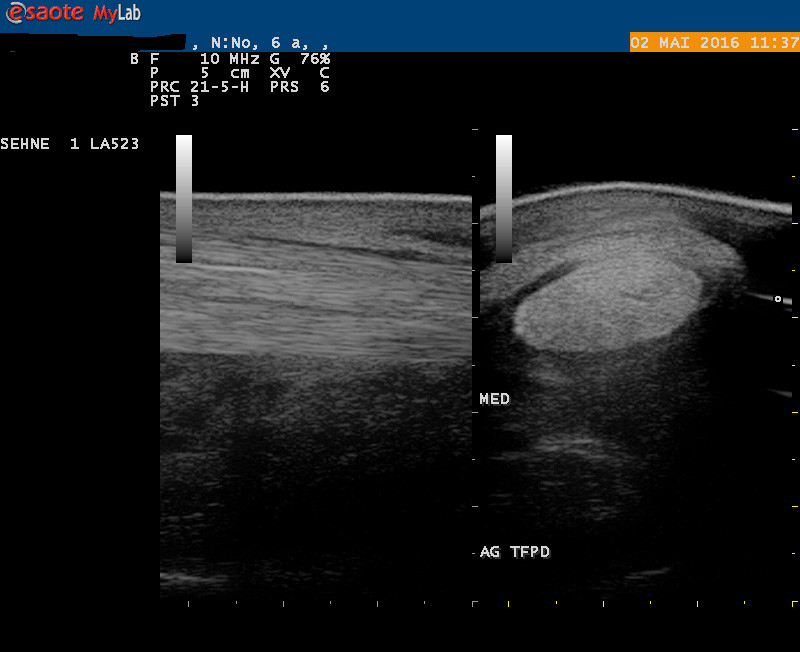

Bildgebung

Ultraschall: Gliedmassen, Sehnen, Gynäkologie